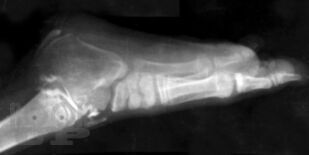

Врожденные пороки развития костей голени у детей

В монографии излагаются результаты многолетнихисследований, проведенныхв научно-исследовательском детском ортопедическом институте им. Г. И. Турнера. Рассматриваются вопросы клиники, диагностики и лечения врожденныхпороков развития костей голени у детей в возрасте от 3 мес. до 15 лет и старше. Описываются новые методики операций, основанные на сберегательной тактике, адекватные различным вариантам порока, позволяющие восстановить форму и функции конечности, техразновидностей порока развития костей голени, которые до настоящего времени считались неоперабельными и подлежали только ампутации. Монография предназначена для ортопедов, травматологов и хирургов.